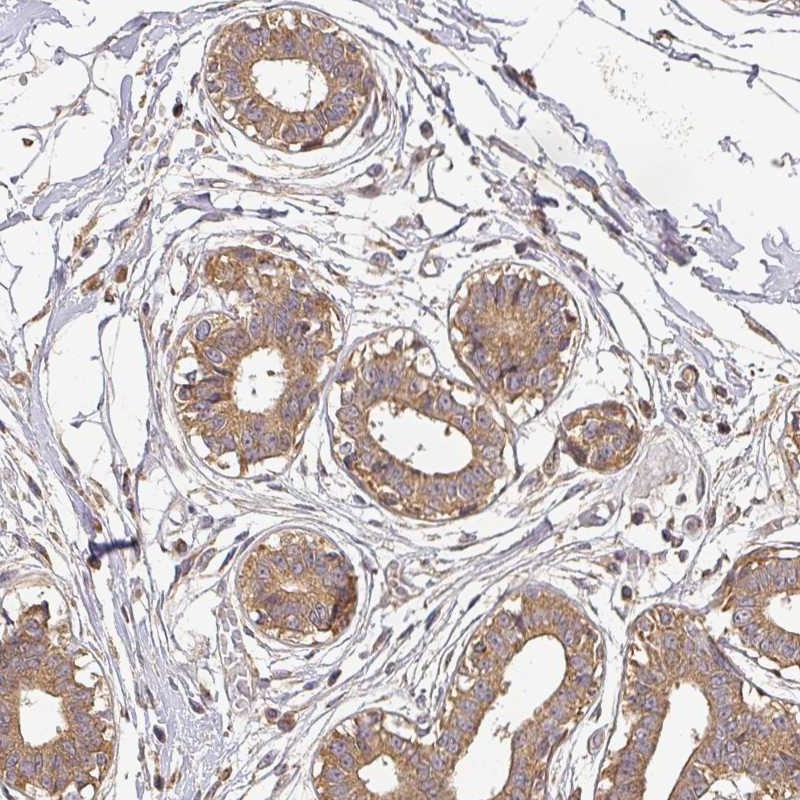

Immunohistochemical staining of human breast shows moderate cytoplasmic positivity in glandular cells.